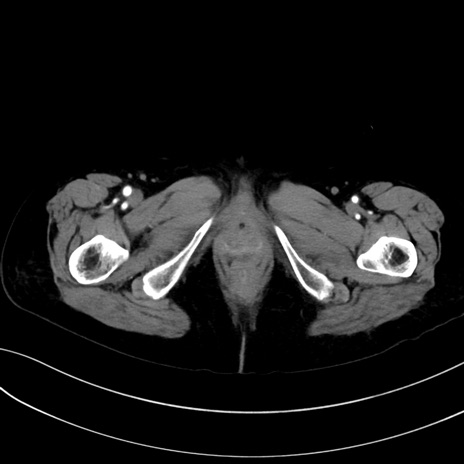

症例13 CT(横断像)1日半後

(冠状断像)1日半後